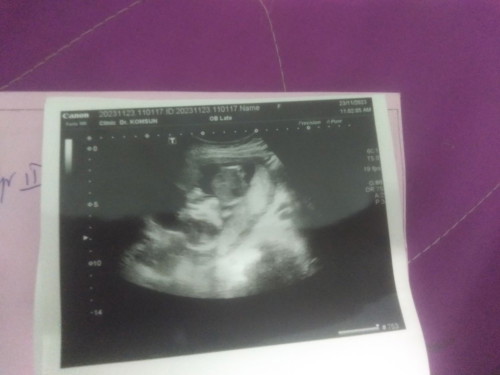

ท้องแรกทีมพฤษภาคม67

คิดว่าเป็นเพศไหนค่ะแม่ๆลุงหมอบอกว่าอีก2เดือนถึงจะรู้เพศ ลุงหมอบอกดิ้นเก่งมากค่ะ ไม่มีแพ้ท้องเลยค่ะ🤗❤️